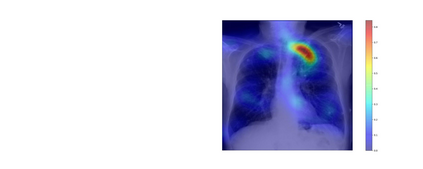

The way humans attend to, process and classify a given image has the potential to vastly benefit the performance of deep learning models. Exploiting where humans are focusing can rectify models when they are deviating from essential features for correct decisions. To validate that human attention contains valuable information for decision-making processes such as fine-grained classification, we compare human attention and model explanations in discovering important features. Towards this goal, we collect human gaze data for the fine-grained classification dataset CUB and build a dataset named CUB-GHA (Gaze-based Human Attention). Furthermore, we propose the Gaze Augmentation Training (GAT) and Knowledge Fusion Network (KFN) to integrate human gaze knowledge into classification models. We implement our proposals in CUB-GHA and the recently released medical dataset CXR-Eye of chest X-ray images, which includes gaze data collected from a radiologist. Our result reveals that integrating human attention knowledge benefits classification effectively, e.g. improving the baseline by 4.38% on CXR. Hence, our work provides not only valuable insights into understanding human attention in fine-grained classification, but also contributes to future research in integrating human gaze with computer vision tasks. CUB-GHA and code are available at https://github.com/yaorong0921/CUB-GHA.